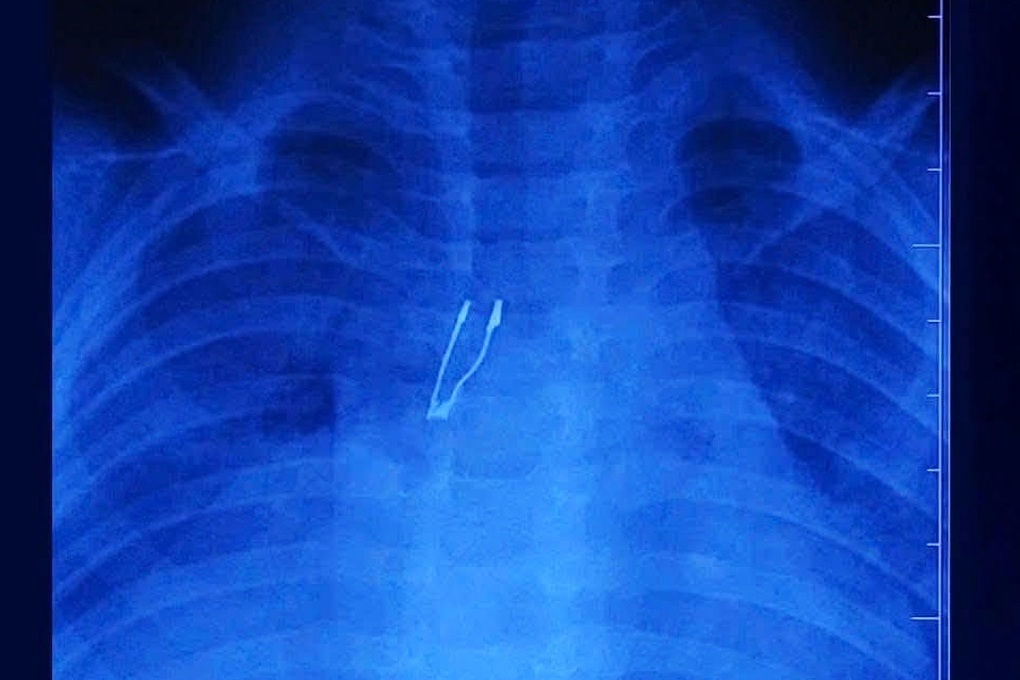

Bệnh nhi là bé N. (9 tháng tuổi, trú tại Đồng Tháp) đi khám vì ho nhiều trong 2 ngày. Tại cơ sở y tế địa phương, các bác sĩ chụp X-quang và phát hiện có dị vật bất thường, nên chuyển thẳng bệnh nhi lên tuyến trên. Đáng chú ý, gia đình không nắm được thời điểm bé ngậm và sặc dị vật, cũng không biết bệnh nhi nuốt gì.

Tại Bệnh viện Nhi đồng 1, kết quả chụp chiếu hình ảnh cho thấy dị vật nằm ở phế quản gốc phải, kèm theo dấu hiệu xẹp phổi phải và tràn khí trung thất – những biến chứng báo hiệu tình trạng phức tạp.